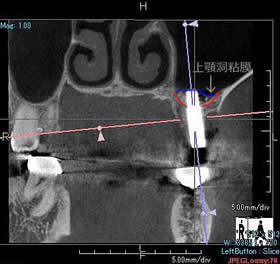

volumeをXYZ方向にそれぞれ512分割しておりこのときのスライスピッチは標準モード撮影で147㎛、高解像度モード撮影(ハイレゾ)で101㎛です。 3D画像はリアルタイムで自由に動かすことができるので骨の形態や奥行きを容易に把握できます。 さらにウィンドウレベルを操作することでさまざまな画像を簡単に得ることができます。 またインプラント治療においては下顎管やオトガイ孔、上顎洞下壁までの距離を正確に測定できるので術中も安全に治療をおこなうことができます。 |

前頭断での術前シュミレーション

(直径5㎜被覆長8㎜での想定)

矢状断での術前シュミレーション

(約3㎜程度のソケットリフトが必要)